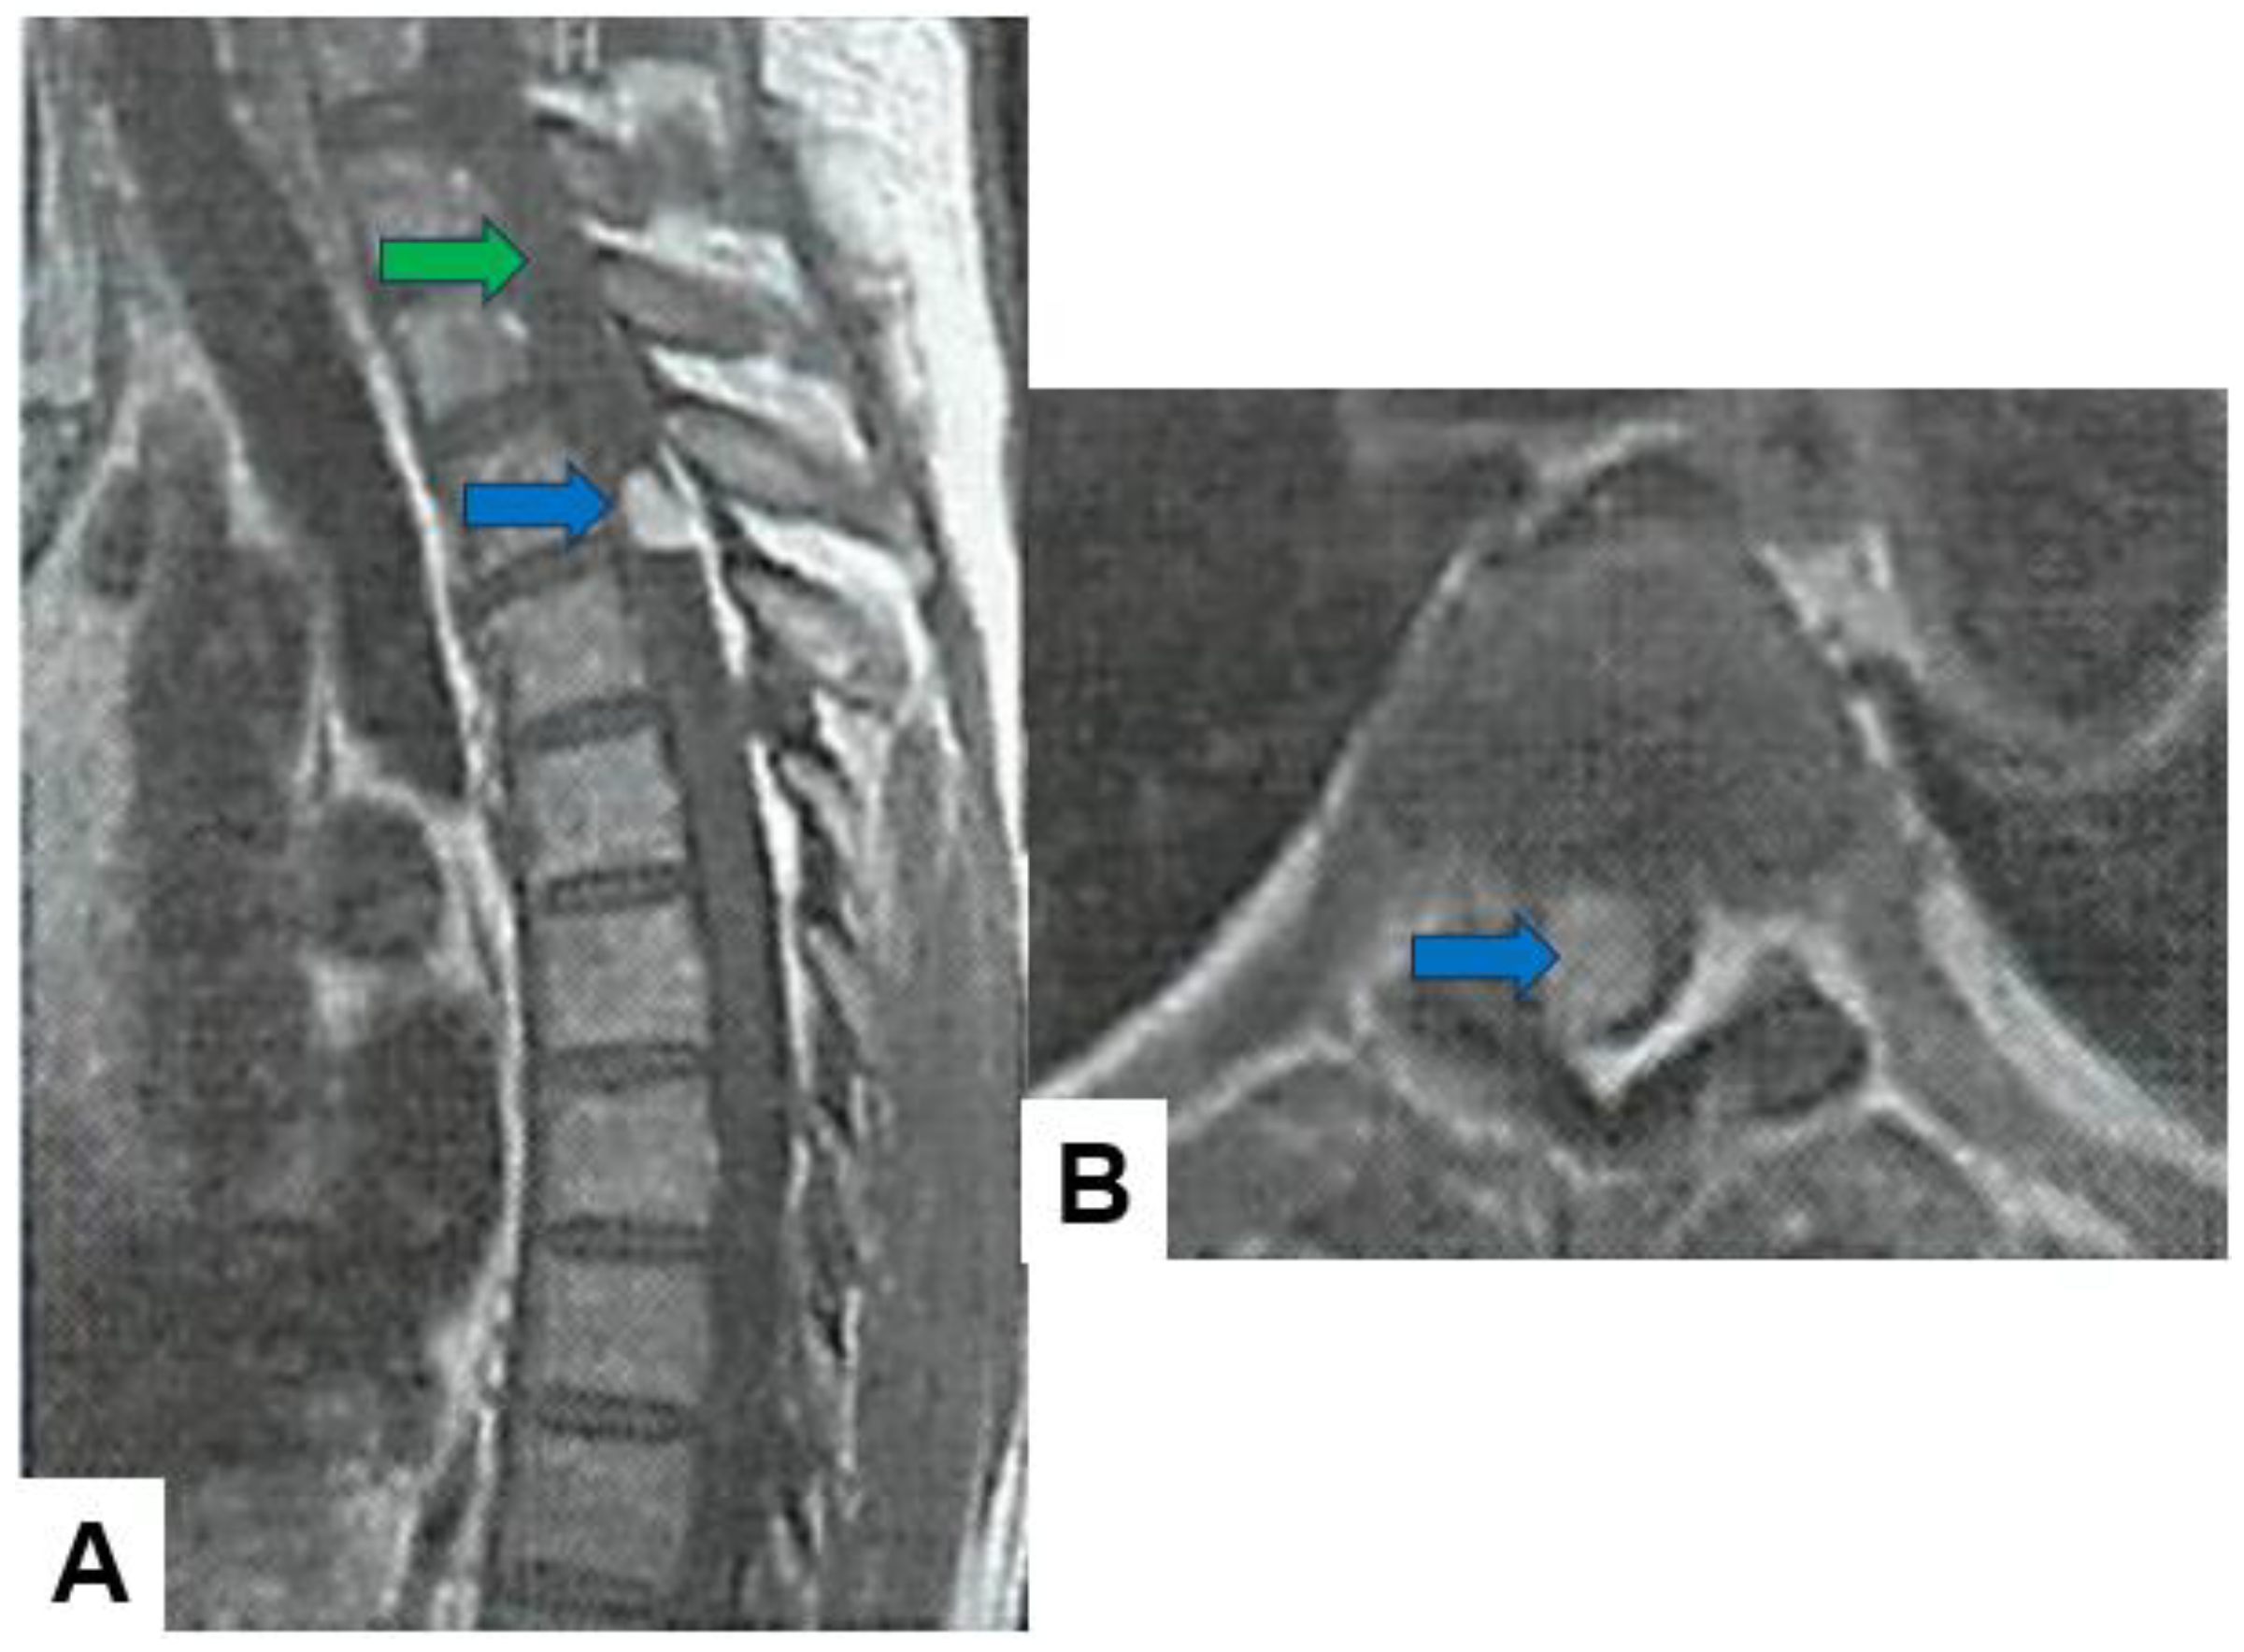

Schwannomas usually show low intensity in T1-weighted MR imaging and high intensity in T2-weighted MR imaging (Figure 1 and Figure 2). These tumors often enlarge alongside the nerve root and become a dumbbell-type [34]. The heterogenicity of a tumor indicates cystic change.

Figure 1.

Fifty-four M, spinal schwannoma. (A) T1-weighted midsagittal image, (B) T2-weighted midsagittal image, and (C) enhanced T1-weighted midsagittal image. Red arrows indicate tumor and blue arrow shows tumor enhancement. The tumor is mixed-intensity because of tumor necrosis.